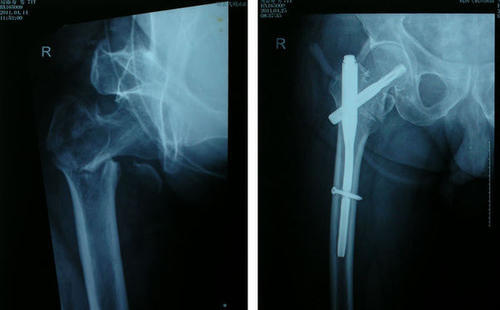

68岁阚先生,身体还算可以,虽然也有高血压,高血脂,但是药物控制的一直还算不错。阚先生也比较注重健康,每天坚持锻炼,这天早晨锻炼,由于刚刚下过雨,路面湿滑。阚先生不小心摔了一跤,送医后发现是髋部骨折。经过医生的评估,建议老人手术治疗,但是家人感觉这么大岁数了,手术治疗怕老爷子受罪,最后还是坚持保守治疗,可是在一年后,老人家却撒手人寰。为什么这个骨折这么致命呢?

髋部骨折又被称为“人生的最后一次骨折”,听着就非常的恐怖,尤其是老年人,髋部骨折很多人都熬不过来,总是因为种种原因而去世。其实骨折是非常常见的现象,碰撞,摔倒等都有可能发生,但是很少出现因为骨折导致死亡。但是髋部骨折却不一样,尤其是中老年人,有研究数据显示,在老年人群中,髋部骨折一年后,生存率仅有50%左右,也就是说,有一半的老人,在髋部骨折后1年内离开了,可见它的严重性有多大。

四、手术治疗还是保守治疗?

一般情况下,髋部骨折强烈建议积极进行手术治疗,这样可以尽快的缓解患者的痛苦,及早的自由活动,减少并发症的发生,研究发现,髋部骨折患者,绝大部分不是因为骨折本身去世,而是因为各种并发症。

但是手术治疗适合每一个人吗?不是的,对于一些基础疾病多,身体极度虚弱,不能耐受手术的患者只能保守治疗。